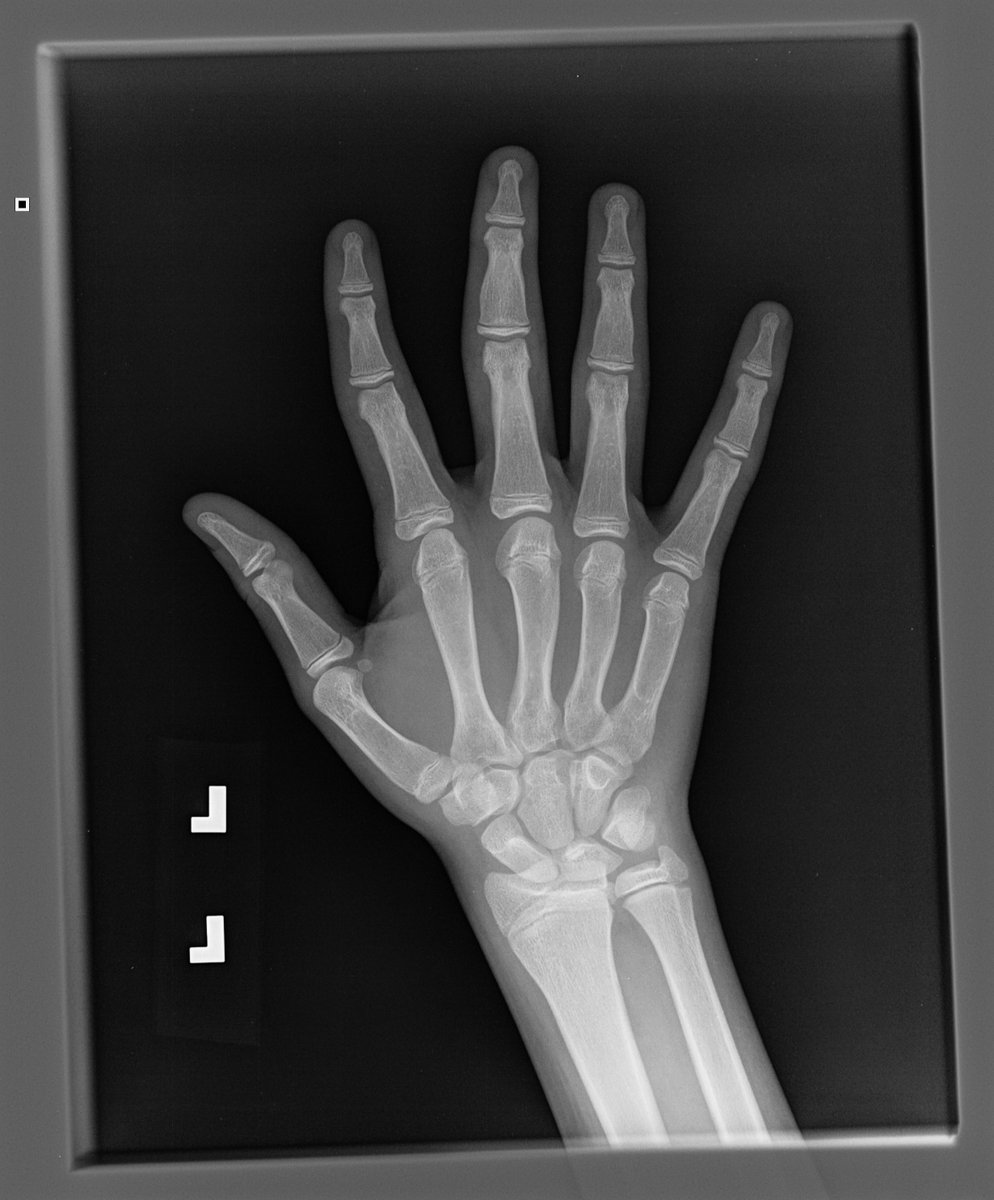

You might have already seen that there are also x-rays within #GestaltMatcher database. Sebastian Rassmann et al. are working on classifiers for rare skeletal malformations based on that data. Check out his poster at #AGD2021

Rare #genetic disorders collectively affect more than 6% of the global population and skeletal dysplasia constitute an important group of such disorders. Due to their rarity, their accurate #diagnosis is a very challenging process ... (1/2)